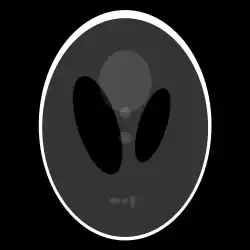

Example of reconstruction via the Radon transform using observations from different angles. The applied inversion to the projection data then reconstructs the slice image.[2]

The process of reconstruction produces the image (or function in the previous section) from its projection data. Reconstruction is an inverse problem.

Compared with the Filtered Back-projection method, iterative reconstruction costs large computation time, limiting its practical use. However, due to the ill-posedness of Radon Inversion, the Filtered Back-projection method may be infeasible in the presence of discontinuity or noise. Iterative reconstruction methods (e.g. iterative Sparse Asymptotic Minimum Variance[10]) could provide metal artefact reduction, noise and dose reduction for the reconstructed result that attract much research interest around the world.

Explicit and computationally efficient inversion formulas for the Radon transform and its dual are available. The Radon transform in dimensions can be inverted by the formula:[11] where , and the power of the Laplacian is defined as a pseudo-differential operator if necessary by the Fourier transform: For computational purposes, the power of the Laplacian is commuted with the dual transform to give:[12] where is the Hilbert transform with respect to the s variable. In two dimensions, the operator appears in image processing as a ramp filter.[13] One can prove directly from the Fourier slice theorem and change of variables for integration that for a compactly supported continuous function of two variables: Thus in an image processing context the original image can be recovered from the 'sinogram' data by applying a ramp filter (in the variable) and then back-projecting. As the filtering step can be performed efficiently (for example using digital signal processing techniques) and the back projection step is simply an accumulation of values in the pixels of the image, this results in a highly efficient, and hence widely used, algorithm.